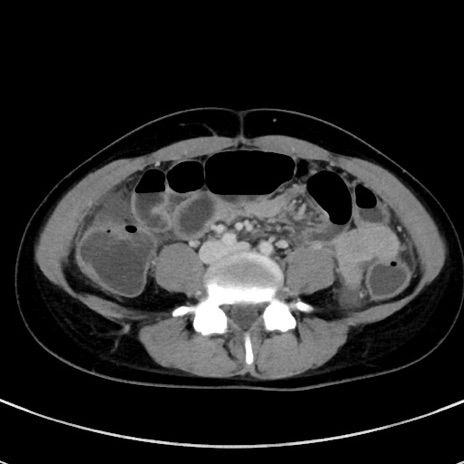

症例17(横断像)

【症例】20歳代女性

【主訴】嘔吐、下腹部痛

【現病歴】昨日夕食後に嘔吐し下腹部痛が出現。本日になっても嘔吐持続し改善しないため来院。

【身体所見】意識清明、BT 37.2℃、BP 108/67mmHg、腹部:平坦、やや硬、下腹部正中から右にかけて圧痛あり、反跳痛軽度あり、tapping pain(+)。

【データ】WBC 13600、CRP 14.94